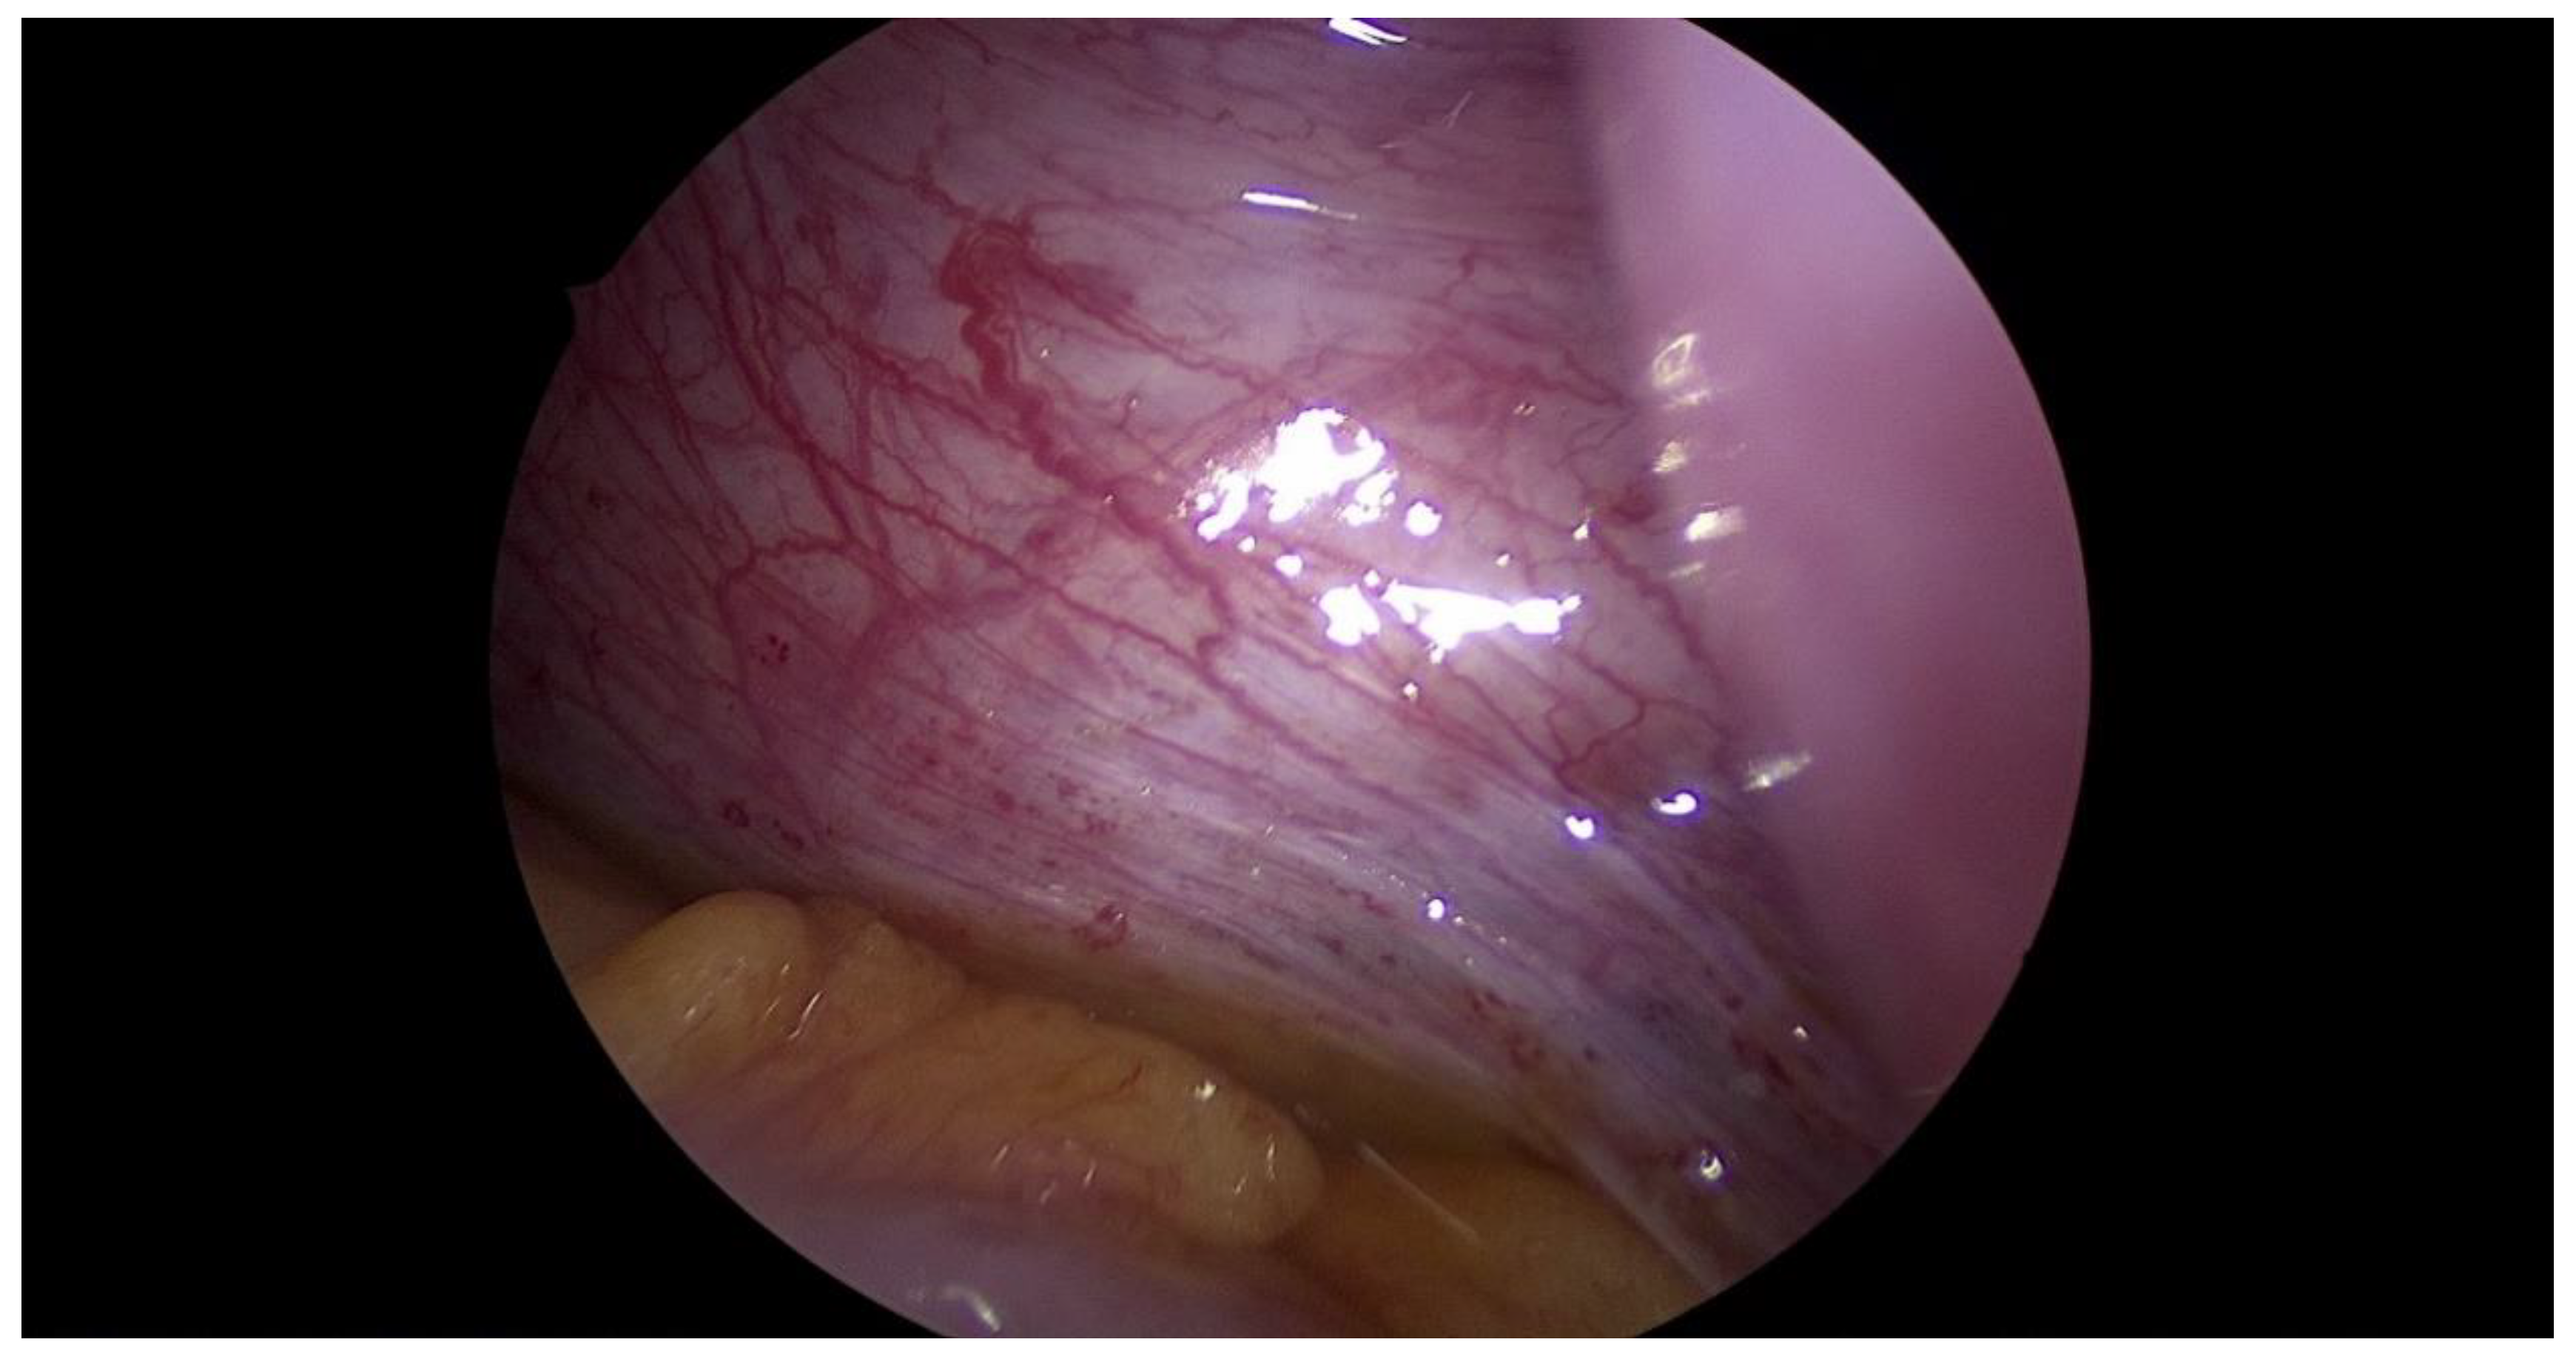

Step 3 Surgical management Surgery is necessary when acute abdominal symptoms are present. “Wait and see” approach is only possible when the clinical situation allows it. Perform laparoscopy and vaginoscopy in order to achieve the correct diagnosis and treat concomitant hematosalpinx and endometriosis [14]. Intraoperative US is helpful to evaluate the place of resection. Unnecessary lengthening the time to diagnosis, contributes to unindentent consequence. |